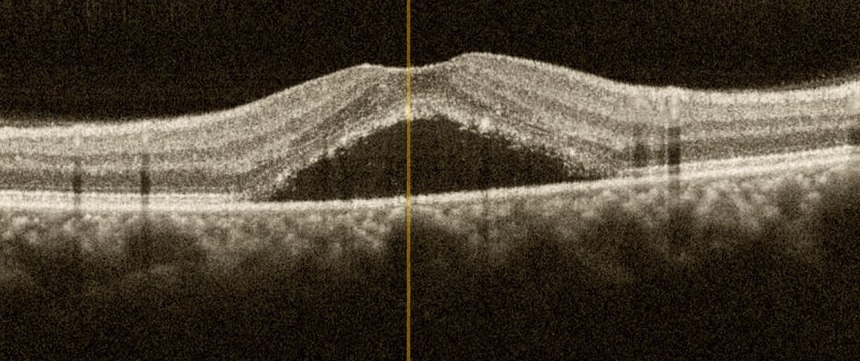

SSR'de OKT görüntüsü

Tanıda rutin göz muayenesine ilave olarak “optik koherens tomografi” yeterli olmakla birlikte, “flöresein anjiyografi” sızıntının yerinin tespitinde ve olası diğer retina hastalıklarının ayırıcı tanısında yararlıdır.